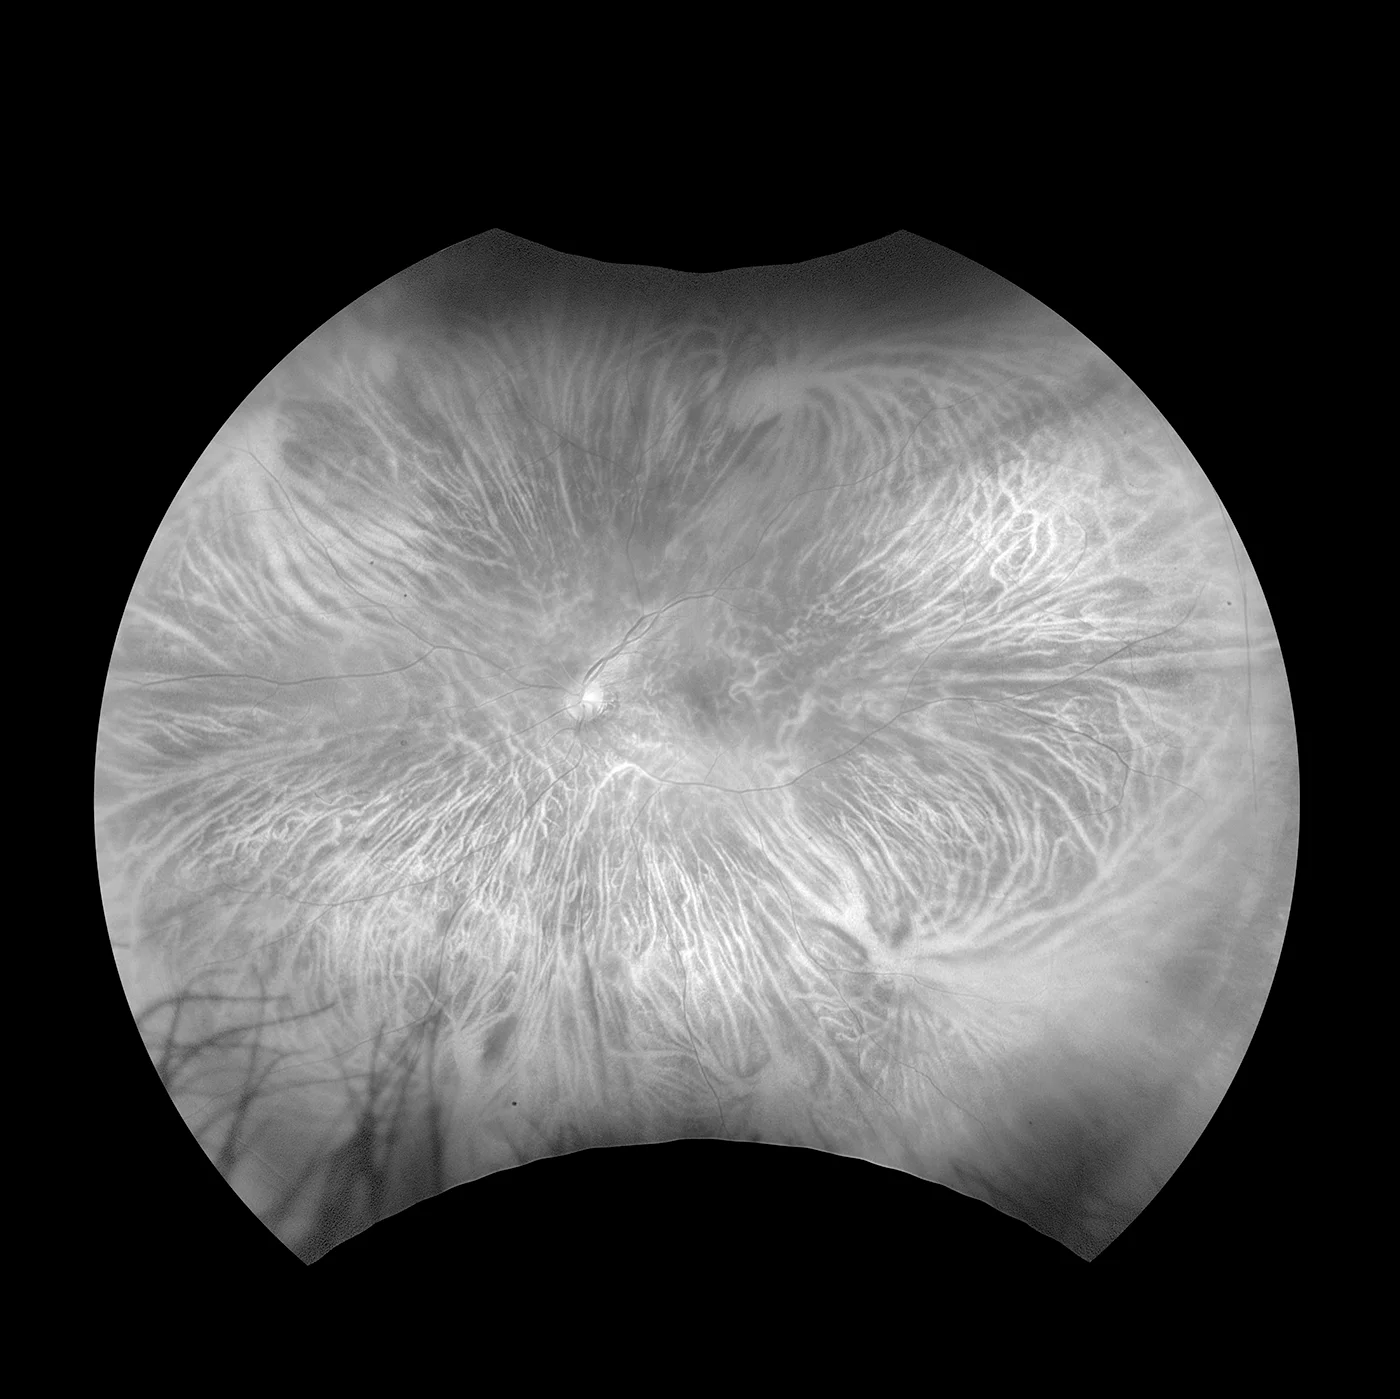

optomap Choroïdienne

Contrairement à la lumière blanche utilisée dans les appareils traditionnels, cette technologie intègre des longueurs d'ondes laser de faible puissance qui effectuent un balayage simultané. Cela permet d'examiner séparément les sous-structures de la rétine dans chaque couleur laser. La visualisation choroïdienne effectue un balayage entre l'épithélium pigmentaire et la choroïde.